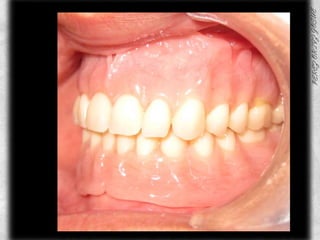

SELECCION DE DIENTESTRILUX     T 41                 COLOR A2, 6247 mm DISTANCIA DE CANINO A CANINO.

MONTAJE DE DIENTES ANTERIORES

MONTAJE DIENTES POSTERIORES

PROTESIS TERMINADA